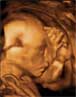

Ecografía 3D de la semana 20: Feto casi al completo

Son visibles su cabeza, brazos y tronco

La ecografía en 3D permite ver al feto con volumen. En la semana 20 de gestación, el feto ya tiene un aspecto muy similar al de un recién nacido, y como aún no es demasiado grande se pueden contemplar en una misma imagen su cabeza, las extremidades y parte del tronco

Feto de 20 semanas casi al completo:

Podemos observar la cabeza, tronco, extremidades, parte del cordón umbilical y, al fondo, la pared uterina.